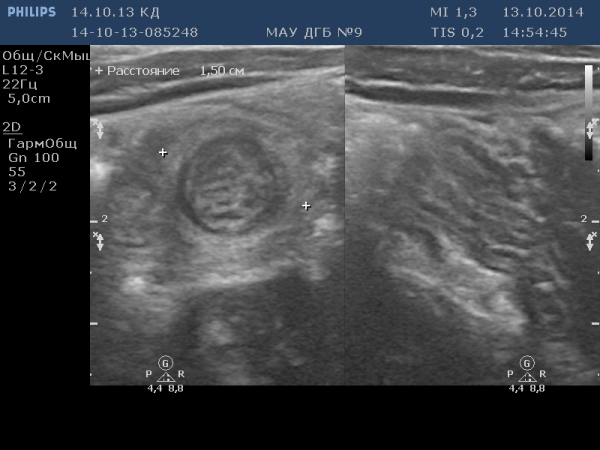

Кишечная инвагинация

Есть моменты напоминающие инвагинацию к-ка, но как-то клиника (стул нормальный, рвоты не было) сюда не вписывается!Кишечная инвагинация

Илья что-то недоговаривает из анамнеза. Какая давность заболевания? Если болеет немного, может и стул быть, рвота как правило при"высокой"непроходимости бывает.

кишечная инвагинанация в типичном месте(подпеченочно справа)+ мезаденит(л.у выступили как якорь и потянули кишку)

Похоже. Действительно, анамнез в студию. Вы же когда смотрели- анамнез знали. Так что нехорош-с батенька задачу нам усложнять.Кишечная инвагинация